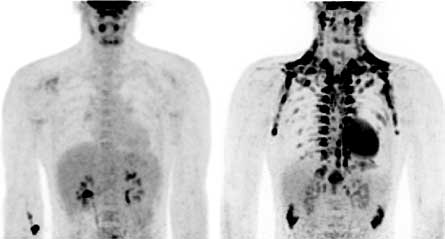

White fat cells store energy in the form of lipids, but brown fat cells burn energy and give off heat. Mice and human babies have pads of brown fat on their backs that help maintain body temperature. Brown fat is activated by cold temperatures. Mice keep the fat throughout life, but brown fat disappears from babies’ backs and many researchers thought adult humans didn’t have brown fat. Or if they did, that it wasn’t important.

Now, the new studies demonstrate that brown fat is common in adults and may be important for regulating body weight and blood sugar. But the fat isn’t where people expected to find it. In adults, brown fat is found in the neck, above the collarbone, around the spine and in the abdomen.

In another study, a team of researchers led by Wouter van Marken Lichtenbelt, a physiologist at the Maastricht University Medical Center in the Netherlands, scanned lean and overweight men at room temperature (22º Celsius or about 72º Fahrenheit) and 16ºC (about 61ºF). The researchers could see almost no brown fat in the room temperature scans, but the brown fat was readily apparent in lean men exposed to the cold. The more overweight the men in the study were, the less brown fat activity researchers detected.